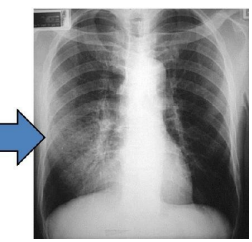

Correct ETT Placement on CXR

Normal tip: 3-5 cm above carina

Case courtesy of Jeremy Jones, <a>Radiopaedia.org</a>. From the case <a>rID: 13260</a>